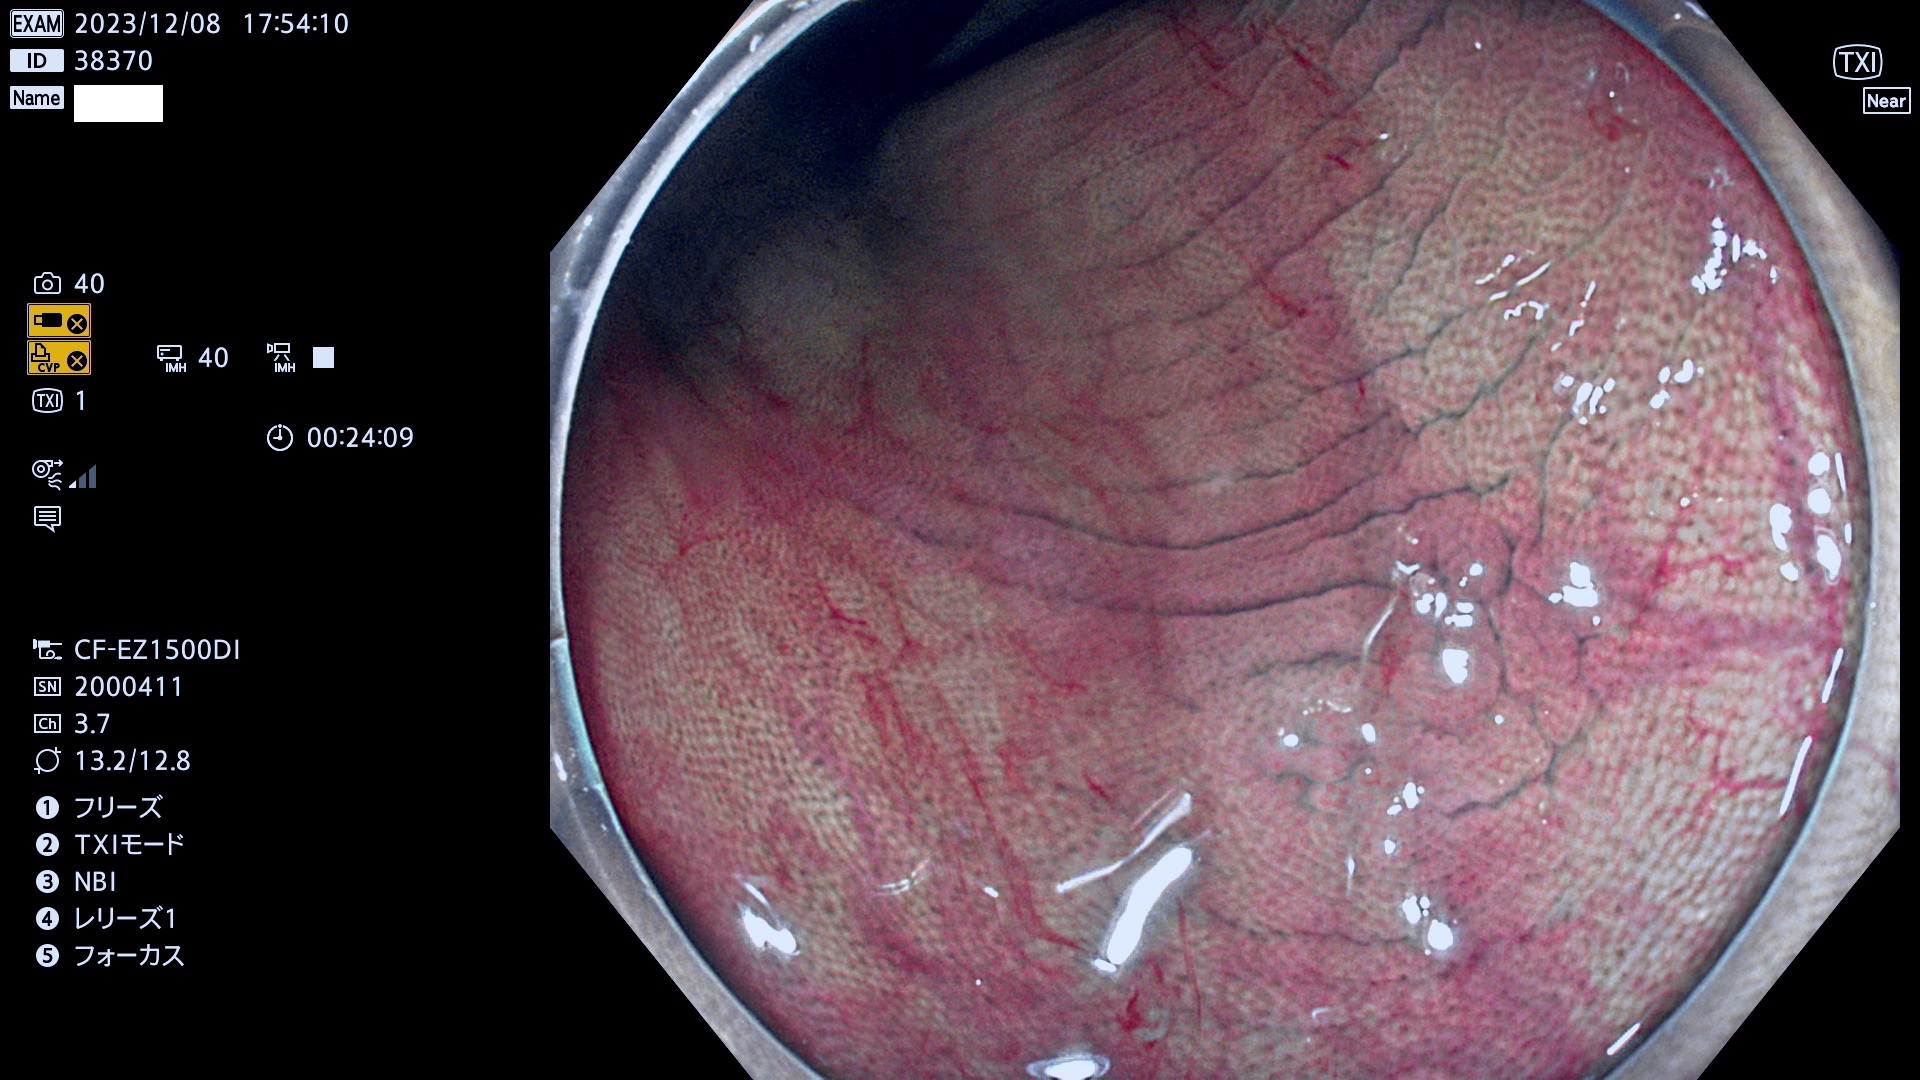

表面型腺腫(Flat Adenoma)の中で、完全に平坦な物をUb、陥凹している物をUcと呼びます。平坦隆起型(Ua)よりも、発見が難しく危険な病変です。このタイプは「内視鏡後・大腸癌の重要犯人」であり、この発見率は「腺腫発見率」よりも、重要な意味があります。

毎週の検査(木・金・土・日)に発見されたUb、Uc型・腺腫を、その週の日曜の夜にUPし1週間、提示します。

抽出の対象期間 2023年12月7日(木)〜12月10(日)の4日間(48件の検査)12件